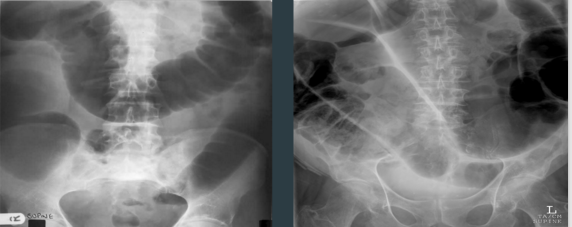

LARGE BOWEL OBSTRUCTION

TWO PATIENTS WITH